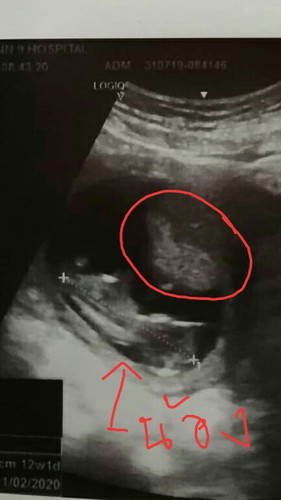

อัลตร้าซาวน์มาตอน12w อยากทราบตรงเราที่วงกลม คืออะไรหรอค่ะ

น่าจะเป็นรกค่ะ